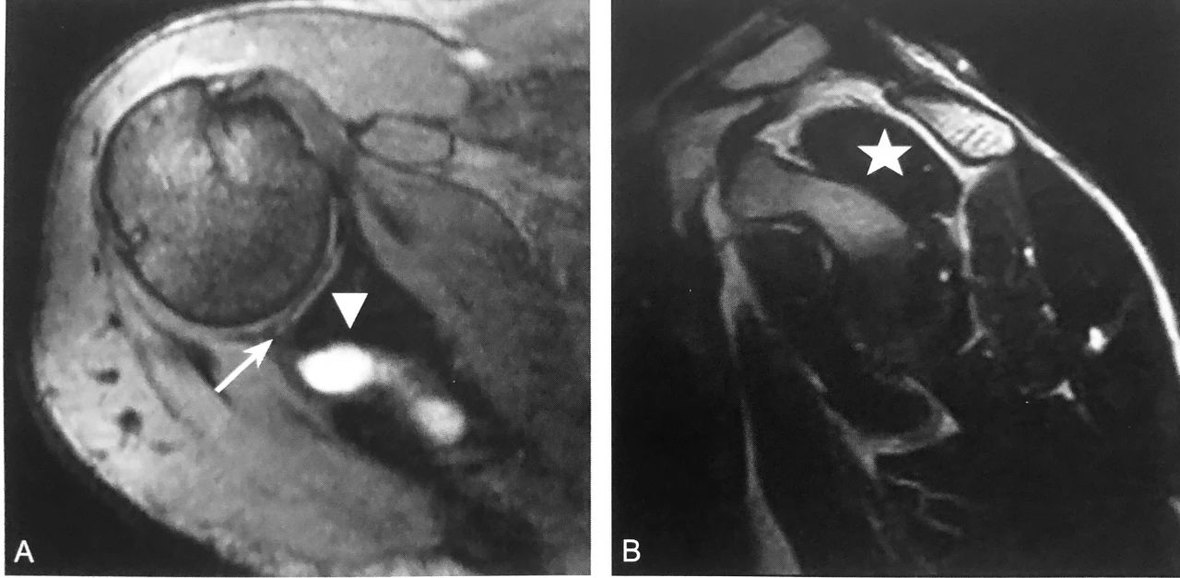

孟 唇 旁 囊 肿

盂唇旁囊肿:A 图横断位压脂 T2 序列显示,后上盂唇撕裂(箭头),伴肩胛上切迹内囊肿(三角);B 图矢状位 T2 序列显示由于肩胛上神经受压所致的冈上肌萎缩(五角星),表现为冈上肌形态缩小,周围被脂肪组织浸润替代

判读要点:

1、囊肿位于盂唇旁软组织内,发现囊肿时,应进一步全面评估盂唇损伤;

2、囊肿表现为单房或多房,增强无强化或边缘轻度强化;

3、囊肿位于肩胛上区及四边孔附近时,需观察神经有无卡压,可行 MRI 或 CT 肩关节造影;

4、同时观察冈上肌、冈下肌、三角肌、小圆肌等有无萎缩。